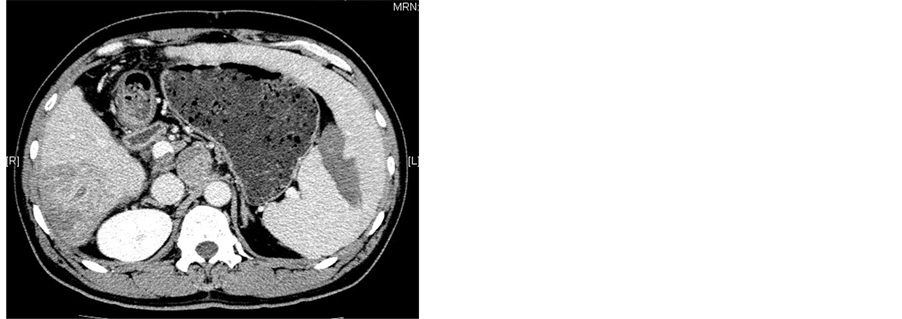

All patients underwent abdominal CT scanning (GE Medical Systems) 1 wk before procedure and 2 wk after procedure to evaluate the necrosis of the spleen (Figure 2). After treatment with MWA combineed with TACE, all patients remained in hospital with their adverse effects or complications observed and were then followed up at outpatient clinic. Peripheral blood cell parameters including white blood cells (WBC), platelets (PLT) and red blood cells (RBC) were obtained 1 wk before procedure and 1 wk, 2 wk, 1 mo, 2 mo, 3 mo after procedure.

Figure 2. (a)-(c) Contrast-enhanced CT scans of the spleen before splenic MWA; (d)-(f) Two weeks after MWA. Contrast-enhanced CT scans showed unenhanced low attenuation ablated area in inferior part of spleen. The ablation ratio was about 20%.